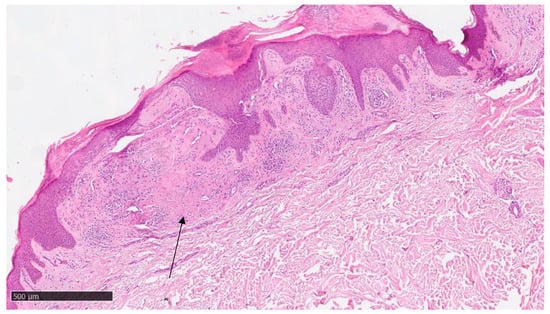

At our clinic, for a diagnosis of certainty regarding LA, an incisional biopsy was performed regarding the typical infiltrated plaques on the lower limbs. The histopathological investigations reported typical LA findings, such as the deposition of amyloid material at the papillary dermis, beneath the dermo-epidermal junction; there were also some areas with inconsistency regarding the melanic pigment and diffuse inflammatory infiltrate at the middle and superficial dermis. The epidermis was not interested in this infiltration and acts as an innocent bystander with acanthosis, hyperkeratosis, and elongation of the epidermal ridges (Figure 3, Figure 4 and Figure 5). With polarized microscopy, it was possible to appreciate the amyloid deposits beneath the dermo-epidermal junction (Figure 6).

Figure 6. Histological photomicrograph showing characteristic apple green birefringence at polarized microscopy (preparation for Congo Red; original magnification 20×).